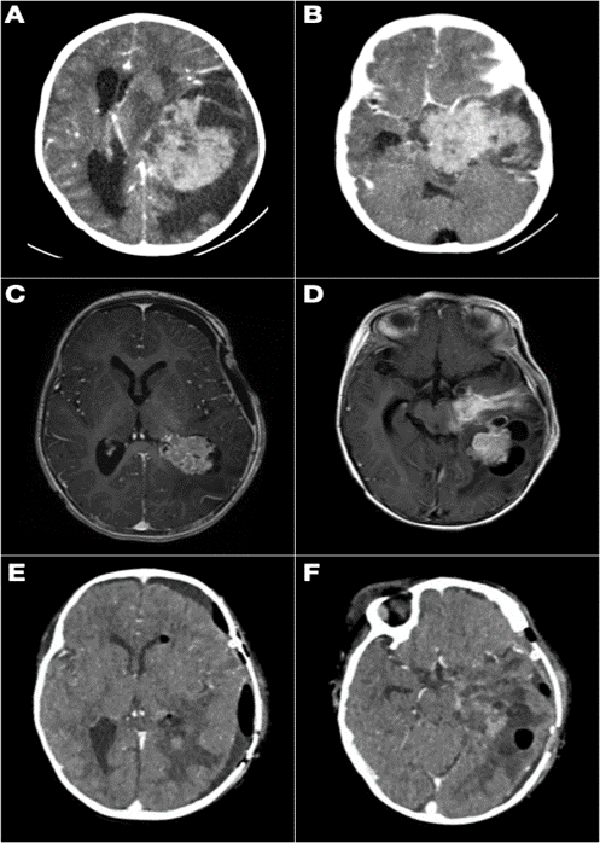

Figura 8: A y B) Paciente de 21 meses de vida, sexo femenino, que presentó hemiparesia faciobraquiocrural derecha, vómitos y deterioro del sensorio, TC de cerebro con contraste EV, lesión supra e infratentorial, con gran efecto de masa con compresión del tronco del encéfalo. Se realizó cirugía de exploración y exéresis parcial. Anatomía patológica informó papiloma de plexos coroideos. C y D) IRM de cerebro con contraste EV que evidenció resto tumoral intraventricular y en relación a cisternas peri mesencefálicas. Se realizó re exploración del tumor. E y F) Imagen por TC de cerebro con contraste EV postquirúrgica inmediata que evidenció exéresis total.